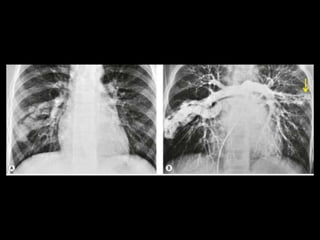

Malformação arteriovenosa(MAV) MAV congênitas: fístulas vasculares com comunicação entre a artéria e a veia pulmonar(95%) ou de uma artéria sistêmica e a veia pulmonar com by-pass do leito capilar; Cerca de 50% das MAVs estão associadas com Síndrome de Rendu-Osler-Weber(teleangiectasia hemorrágica hereditária); O diagnóstico costuma ser bem direto pela TC;

Malformação arteriovenosa(MAV) TC:o aspecto típico é de uma massa regular, lobulada, redonda ou oval, ou até o de uma formação serpenginosa, com menos de 1 cm a vários cm de tamanho, associada a uma artéria nutriz visivelmente aumentada e uma veia de drenagem alargada; Uma ANGIO-TC geralmente faz o diagnóstico; Tratamento pode ser realizado com terapia embólica.

• 19.

• 21.